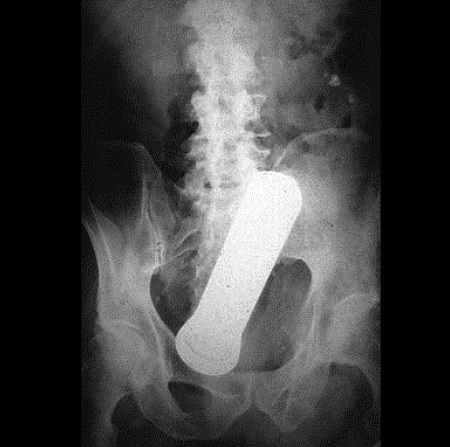

Malum Bölgelerine Kazayla Giren Nesneler Sonucu Acile Kaldırılmış İnsanl galerisi resim 4

• 4 / 15

Malum Bölgelerine Kazayla Giren Nesneler Sonucu Acile Kaldırılmış İnsanların 15 Röntgen Görüntüsü  Bu nesnelerin orada olmasının mantıklı hiçbir alakası yok. Büyük ihtimalle bir kaza sonucu bu durum oluşmuştur. Aksini düşünmek bile istemiyorum. Foto Galerimizin devamını görmek için Lütfen sonraki sayfaya geçiniz..